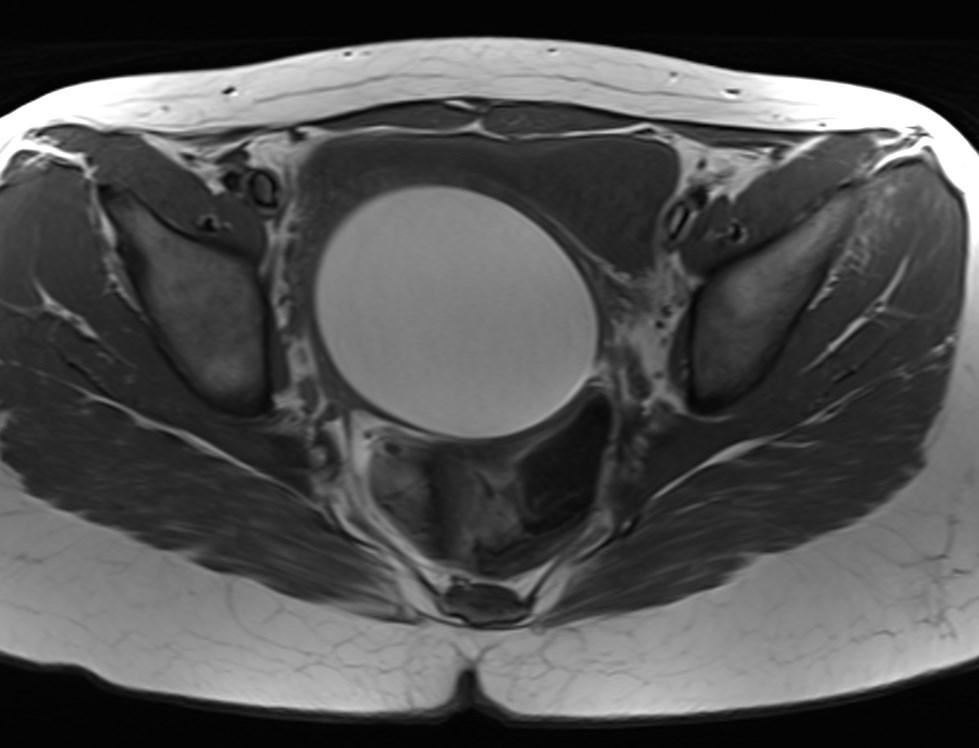

MR images showed hemorrhagic fluid in a distended vagina. The uterine cavity is not dilated.

In haematocolpos, there is accumulation of menstrual blood in the vagina in the setting of an anatomical obstruction, usually an imperforate hymen. When there is concurrent uterine distention, the term haematometrocolpos is used.